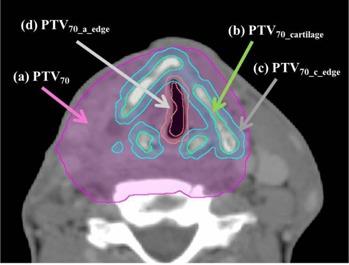

In this study, we assessed the differences in the dose distribution of a 4 MV photon beam among different calculation algorithms: the Acuros XB (AXB) algorithm, the analytic anisotropic algorithm (AAA), and the pencil beam convolution (PBC) algorithm (ver. 11.0.31), in phantoms and in clinical intensity-modulated radiation therapy (IMRT) plans. Homogeneous and heterogeneous, including middle-, low-, and high-density, phantoms were combined to assess the percentage depth dose and lateral dose profiles among AXB, AAA, and PBC. For the phantom containing the low-density area, AXB was in agreement with measurement within 0.5%, while the greatest differences between the AAA and PBC calculations and measurement were 2.7% and 3.6%, respectively. AXB showed agreement with measurement within 2.5% at the high-density area, while AAA and PBC overestimated the dose by more than 4.5% and 4.0%, respectively. Furthermore, 15 IMRT plans, calculated using AXB, for oropharyngeal, hypopharyngeal, and laryngeal carcinomas were analyzed. The dose prescription was 70 Gy to 50% of the planning target volume (PTV70). Subsequently, each plan was recalculated using AAA and PBC while maintaining the AXB-calculated monitor units, leaf motion, and beam arrangement. Additionally, nine hypopharyngeal and laryngeal cancer patients were analyzed in terms of PTV70 for cartilaginous structures (PTV(70_cartilage)). The doses covering 50% to PTV70 calculated by AAA and PBC were 2.1% ± 1.0% and 3.7% ± 0.8% significantly higher than those using AXB, respectively (p < 0.01). The increases in doses to PTV(70_cartilage) calculated by AAA and PBC relative to AXB were 3.9% and 5.3% on average, respectively, and were relatively greater than those in the entire PTV70. AXB was found to be in better agreement with measurement in phantoms in heterogeneous areas for the 4 MV photon beam. Considering AXB as the standard, AAA and PBC overestimated the IMRT dose for head and neck cancer. The dosimetric differences should not be ignored, particularly with cartilaginous structures in PTV.

在本研究中,我们评估了4兆伏光子束在不同计算算法(Acuros XB(AXB)算法、解析各向异性算法(AAA)和笔形束卷积(PBC)算法(版本11.0.31))之间在体模和临床调强放射治疗(IMRT)计划中的剂量分布差异。将均匀和非均匀(包括中密度、低密度和高密度)体模组合起来,以评估AXB、AAA和PBC之间的百分深度剂量和侧向剂量分布。对于包含低密度区域的体模,AXB与测量值的一致性在0.5%以内,而AAA和PBC计算值与测量值之间的最大差异分别为2.7%和3.6%。在高密度区域,AXB与测量值的一致性在2.5%以内,而AAA和PBC分别将剂量高估了4.5%以上和4.0%以上。此外,分析了15个使用AXB计算的口咽癌、下咽癌和喉癌的IMRT计划。剂量处方为计划靶体积(PTV70)的50%给予70 Gy。随后,在保持AXB计算的监测单位、叶片运动和射束排列的同时,使用AAA和PBC对每个计划进行重新计算。此外,对9名下咽癌和喉癌患者的软骨结构的PTV70(PTV(70_cartilage))进行了分析。AAA和PBC计算的覆盖PTV70的50%的剂量分别比使用AXB计算的剂量显著高2.1%±1.0%和3.7%±0.8%(p<0.01)。AAA和PBC相对于AXB计算的PTV(70_cartilage)剂量平均分别增加了3.9%和5.3%,且相对大于整个PTV70中的增加量。结果发现,对于4兆伏光子束,AXB在非均匀区域的体模中与测量值的一致性更好。以AXB为标准,AAA和PBC高估了头颈癌的IMRT剂量。剂量学差异不容忽视,尤其是PTV中的软骨结构。